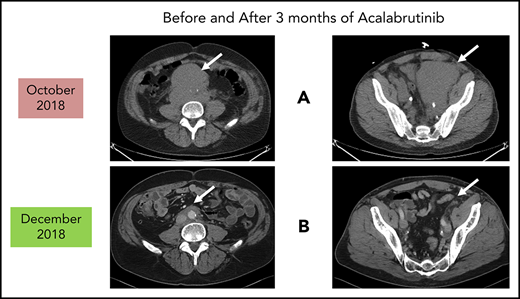

Before and after 3 months of acalabrutinib. A 54-year-old man was diagnosed with stage IVB MCL in 2014. He received chemoimmunotherapy including cytosine arabinoside and an adjuvant autologous SCT. (A) In 2018, he relapsed with left leg swelling due to bulky pelvic disease and a new deep vein thrombosis. (B) After biopsy proof of relapsed MCL, he received acalabrutinib 100 mg twice daily, rituximab, and apixaban; within 3 months, he achieved a marked response with no side effects of the combination. He has returned to full-time work and continues on therapy as of January 2019.

As reported in the clinical trial,43 acalabrutinib at the recommended dose of 100 mg twice daily is well-tolerated as demonstrated by only 1.6% of patients requiring dose reductions and only 6.5% of patients discontinuing acalabrutinib due to adverse events. Of note, atrial fibrillation was not observed in any patient. The most common side effects were headaches (36%) and diarrhea (38%), both of which were typically grades 1-2 and self-limited.43,44 If treatment of these is needed, then oral nonnarcotic agents that do not impair platelet function are recommended. These would include acetaminophen alone or with caffeine. Bleeding events were usually grade 1-2 and consisted of bruising and petechiae; there was 1 case of grade 3 gastrointestinal hemorrhage. Significant myelosuppression can occur and grade 4 neutropenia occurred in 6%. For these grade 3/4 toxicities, dose reductions to 100 mg daily may be required. It is not known what effect dose reduction has on tumor response. In patients such as the 1 described in Figure 1, acalabrutinib at full dose can be given with direct oral anticoagulants with appropriate instructions to watch for bleeding complications.